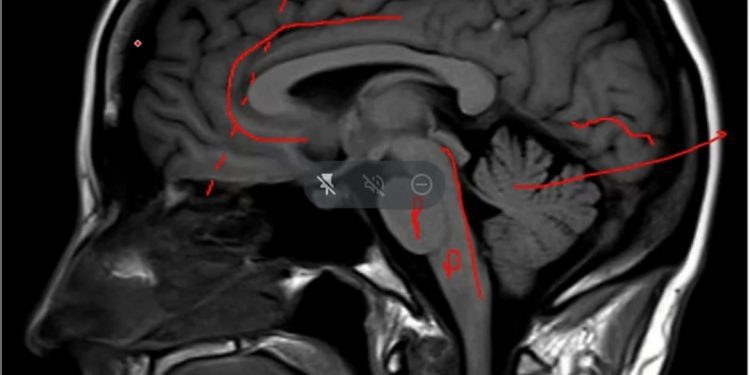

Durante su conferencia, el especialista abordó con ejemplos y explicaciones prácticos las temáticas relacionadas con los neurotransmisores y transmisión de la sustancia; circuito de recompensas y zonas involucradas (corteza prefrontal, sistema límbico); poda sináptica y la relación que tienen con el consumo de drogas algunos fármacos clasificados como “tranquilizantes” , por ejemplo clonazepam, amprazolam o ravotril, en niños, niñas, adolescentes y jóvenes de establecimientos educativos.

Finalmente, Claudio Berríos enfatizó lo peligroso e irremediable del consumo, pues dañan el desarrollo de físico, neurológico y mental. “Las drogas son tremendamente nefastas, porque las drogas parece que en definitiva están produciendo, si se ocupan tempranamente en este chico o chica, están produciendo una alteración de esta modulación y podrían retardar el desarrollo de la corteza prefrontal y en algunos casos dañar, quizás irreversiblemente, el dominio de la corteza cerebral sobre este sistema límbico que es un estallar de emociones de distinta naturaleza”.